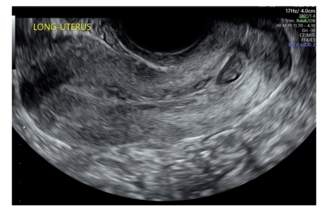

Two cases are presented of patients who had minimal intraoperative blood loss secondary to IR placement of intra-arterial occlusion balloons prior to evacuation of cervical ectopic pregnancy.